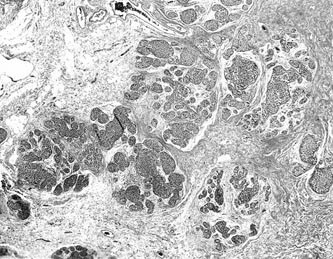

The breast lobules and soft tissue were infiltrated with a malignant population of medium-sized lymphocytes with abundant clear cytoplasm (Figs. 5 and 6). The lobular infiltrate gave the appearance of LE lesions (Fig. 7). The cells in the bronchial biopsy had a similar appearance. No necrosis or vascular invasion was present. The malignant cells were immunoreactive with CD45RB (weak), CD3, CD43, TIA-1, and CD56 (Fig. 8). The cells were negative with CD20, CD45RO, βF1, TCR δ, CD30, CD4, CD8, latent membrane protein for Epstein-Barr virus, and cytokeratin. The diagnosis was revised to NK/T-cell lymphoma. No monoclonal band was found in the IgH or the TCR β or γ assay. The in situ hybridization study for Epstein-Barr virus–encoded RNA was negative.